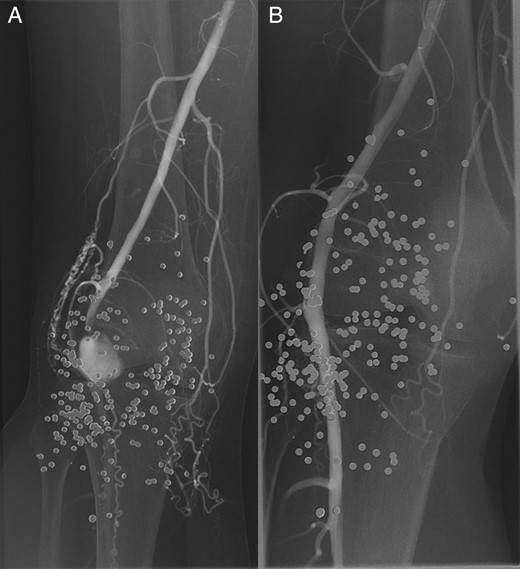

A repeat angiogram after 24 h of thrombolysis demonstrated improved patency while at 48 h excellent patency of the infragenicular vessels was seen (Fig. 2), and the patient was subsequently discharged on dual-antiplatelet and statin therapy. A follow-up arterial Duplex performed at 6 weeks post discharge demonstrated excellent patency of the stent graft and infragenicular arteries.

A digital subtraction angiogram at presentation (A) and after 48 h of continuous alteplase thrombolysis (B) demonstrating the improved patency of the infrapopliteal arteries.